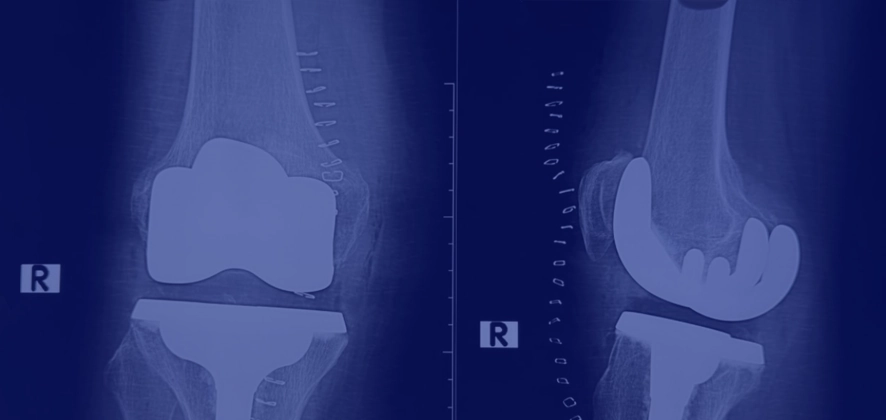

Індивідуальний підхід до створення нових суглобів

Страх перед протезуванням найчастіше живиться міфами про те, що імплантат – це щось неймовірно важке, чужорідне і вкрай незручне. Насправді ж сучасні ендопротези є справжніми шедеврами медичної інженерії. Вони виготовляються з високоміцних біосумісних сплавів (переважно титану та кобальт-хрому), інноваційної кераміки та надзвичайно зносостійкого високополімерного поліетилену. Термін їхньої служби сягає 20-25 років.

- Штучне коліно ідеально імітує складний шарнірний рух з елементами ковзання, забезпечуючи відмінну амортизацію та здатність щоденно витримувати величезну вагу тіла без розхитування.

Встановлення таких високотехнологічних систем відбувається з математичною точністю, що гарантує ідеальне приживлення металевої конструкції до кісткової тканини пацієнта та виключає відчуття чужорідного тіла.